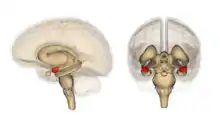

Location of the amygdalae in the human brain

Human brain in the coronal orientation. Amygdalae are shown in dark red.